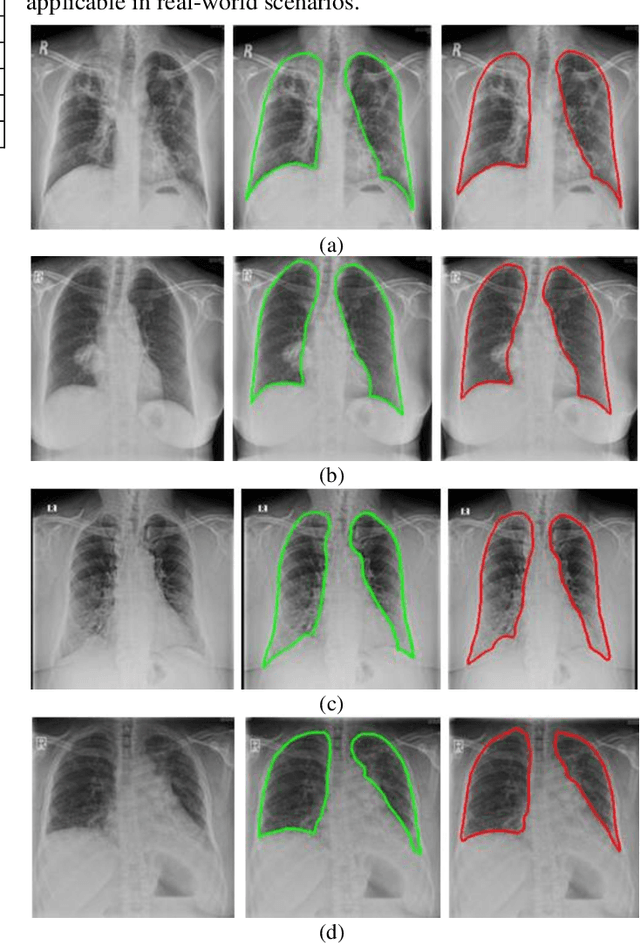

Abstract:A chest radiograph, commonly called chest x-ray (CxR), plays a vital role in the diagnosis of various lung diseases, such as lung cancer, tuberculosis, pneumonia, and many more. Automated segmentation of the lungs is an important step to design a computer-aided diagnostic tool for examination of a CxR. Precise lung segmentation is considered extremely challenging because of variance in the shape of the lung caused by health issues, age, and gender. The proposed work investigates the use of an efficient deep convolutional neural network for accurate segmentation of lungs from CxR. We attempt an end to end DeepLabv3+ network which integrates DeepLab architecture, encoder-decoder, and dilated convolution for semantic lung segmentation with fast training and high accuracy. We experimented with the different pre-trained base networks: Resnet18 and Mobilenetv2, associated with the Deeplabv3+ model for performance analysis. The proposed approach does not require any pre-processing technique on chest x-ray images before being fed to a neural network. Morphological operations were used to remove false positives that occurred during semantic segmentation. We construct a CxR dataset of the Indian population that contain healthy and unhealthy CxRs of clinically confirmed patients of tuberculosis, chronic obstructive pulmonary disease, interstitial lung disease, pleural effusion, and lung cancer. The proposed method is tested on 688 images of our Indian CxR dataset including images with severe abnormal findings to validate its robustness. We also experimented on commonly used benchmark datasets such as Japanese Society of Radiological Technology; Montgomery County, USA; and Shenzhen, China for state-of-the-art comparison. The performance of our method is tested against techniques described in the literature and achieved the highest accuracy for lung segmentation on Indian and public datasets.